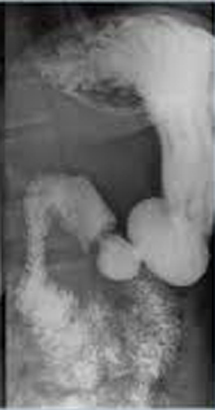

| images TOGD de oesophage

normale |

image TOGD de oesophage (

angle de His ) et estomac normale |